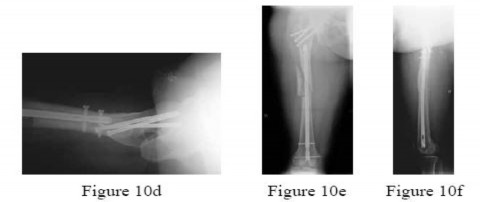

-Figures 10a and 10b are the radiographs of a 33-year-old man who was involved in a high-speed motorcycle crash. He sustained an isolated injury to the right lower extremity. On the day of injury, he was treated with open reduction and internal fixation of the femoral neck and retrograde nailing of the femur.

Radiographs are shown in Figures 10c through 10f. Alternative treatment with a cephalomedullary device alone would be more likely to lead to which of the following outcomes?